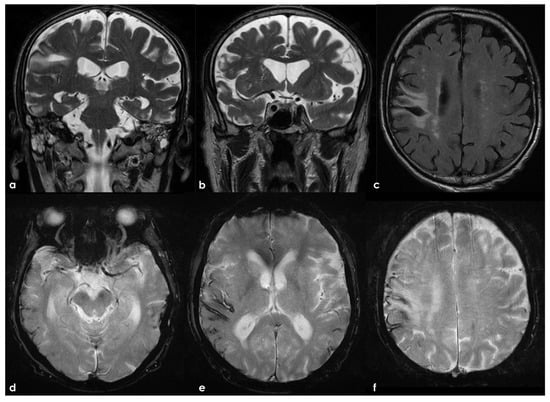

7. Structural Neuroimaging Markers